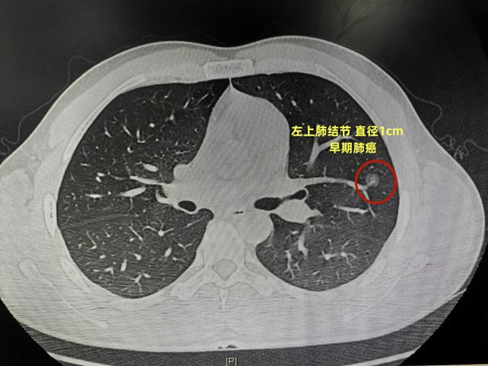

40岁的陈女士,

体检发现左上肺结节,

高度疑似早期肺癌,

需要手术治疗。